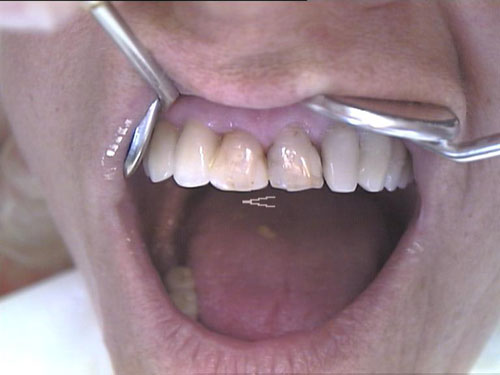

Zahn-Anomalien 1

Zahn-Anomalien 2

Zahn-Anomalien 3

Zahn-Anomalien 4

Zahn-Anomalien 5